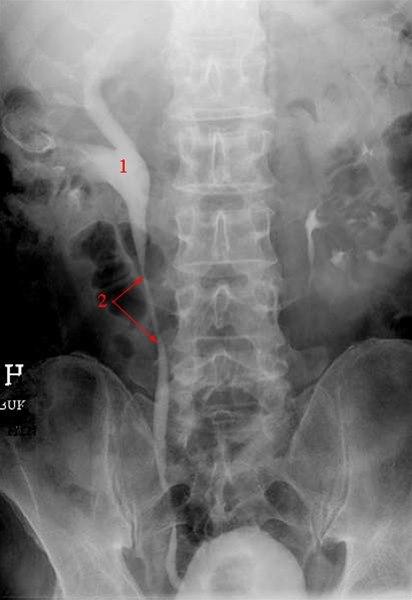

Ved hydronefrose foreligger en utvidelse av samlesystemet. Denne utvidelsen skyldes i de fleste tilfeller et hinder i urinveien nedenfor nyrebekkenet. Konsekvensen blir at urin hoper seg opp ovenfor hindringen, noe som øker trykket i den øvre delen av urinveien, også i nyrebekkenet. Vedvarer trykket lenge nok, vil nyrevevet kunne presses sammen og nyrefunksjonen vil kunne svekkes.

Hydronefrose skyldes en avløpshindring i urinveiene. En slik hindring kan for eksempel være en forstørret prostatakjertel eller en forsnevring i den ene eller begge urinlederne. Dette vil føre til økt trykk i de øvre urinveiene ovenfor det trange partiet, slik at nyrenes samlesystem utvides.